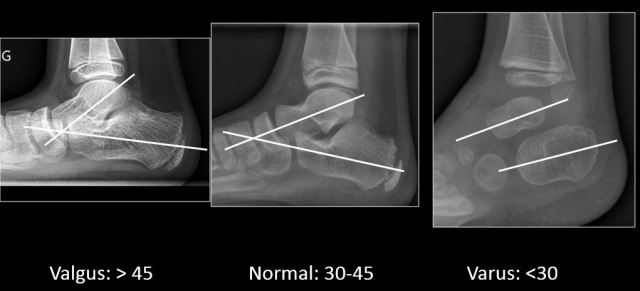

- Talocalcaneal angle: the angle formed between midtalar and midcalcaneal line. Normal: 300-450; <300: varus; >450: valgus.

- Tibiocalcaneal angle: angle formed between the long axis of tibia and mid calcaneal line on lateral radiograph. Normal: 700-900; >900: equinus; <700: calcaneus.

- Valgus: increase in talocalcaneal angle (>450) with midcalcaneal line deviated away from midline.

- Varus: decrease in talocalcaneal angle (<300) with midcalcaneal line deviated towards midline (r in the va’r’us is for ‘reduction’ of angle).

Valgus and varus are best evaluated on AP view while equinus, calcaneus and cavus are best evaluated on lateral view.

- Normally, long axis of talus is directed anteroinferiorly, while that of calcaneum anterosuperiorly. When the calcaneum moves towards the talus i.e. varus, it lifts up the talus and it is vice versa in valgus deformity. Usually the varus deformity is associated with cavus (cavovarus) and planus deformity with valgus.

- Apart from calculating the talocalcaneal angle, also calculate the tibiocalcaneal angle.